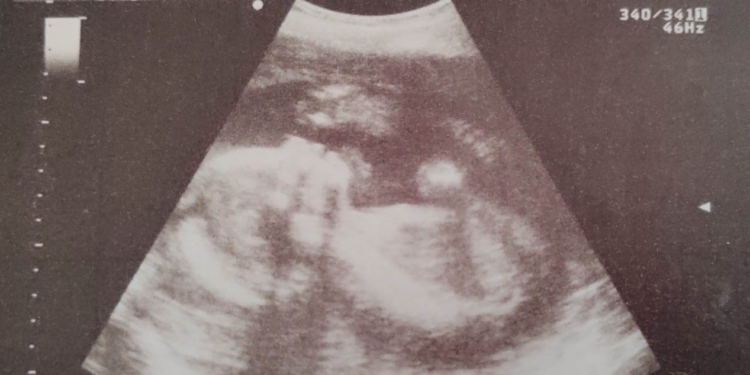

Da femminista quale sono, rivendico i diritti delle donne e il diritto di poter scegliere sulla propria vita. Una gravidanza portata a termine è un piccolo essere vivente che crescerà, avrà bisogno di cure, attenzioni e tutto ciò che serve ad una persona per vivere. Quello che nelle prime settimane è un cumulo di sangue, diventerà in nove mesi un bambino, che sarà un adulto come tutti noi. Metterlo al mondo comporta delle responsabilità, non tutte le donne hanno i mezzi per portare avanti una gravidanza. E preferisco non entrare nel merito dei mezzi che possono essere materiali o immateriali.

Come possiamo entrare nel merito delle scelte personali di una donna che decide che le mancano i mezzi per diventare mamma? Soprattutto quando i mezzi sono immateriali? Chi glieli può fornire? E poi ci sono quei 90 giorni superati i quali il feto, il cumulo di sangue, diventa una persona e secondo la legge non puoi più abortire. In realtà, la 194 fa riferimento anche a casi particolari in cui per motivazioni legate alla salute della mamma o del bambino, è consentito l’aborto anche oltre questo termine. Insomma, direi che la legge ha toccato e regolamentato proprio tutti i punti di vista legati ad una gravidanza. -se sono stata stuprata, non voglio quel bambino che mi ricorderà sempre lo stupro. -se il bambino non è sano, appena lo scopro, posso decidere di non avere la forza di crescerlo. -se sono sola, non ho nessuno, sono moralmente debole, posso decidere che quel bambino avrà una vita di tormenti e voglio evitarlo. …

Ma quando l’aborto diventa un problema? Diventa un problema quando è il piano B per evitare una gravidanza; quando diventa un contracettivo; quando viene preso alla leggera guardando quel piccolo grumo di sangue come se fosse un brufolo da eliminare. Allora sono d’accordo, la legge 194 va rivista e dettagliata meglio. Sono del parere che la gravidanza rappresenti la vita e vada tutelata, così come va tutelato il bambino, o bambina, che sarà pronto a nascere alla fine delle 40 settimane di gestazione.